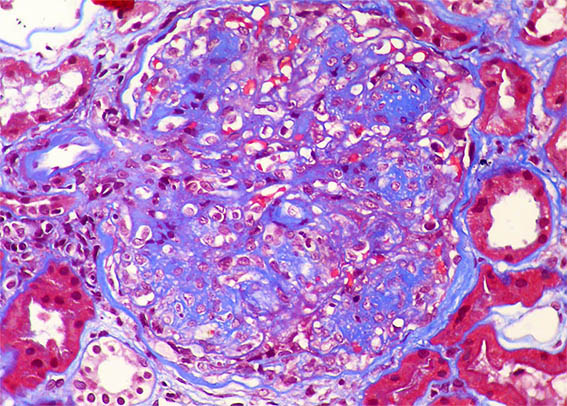

Figura 3.

Tricrómico de Masson, X400.